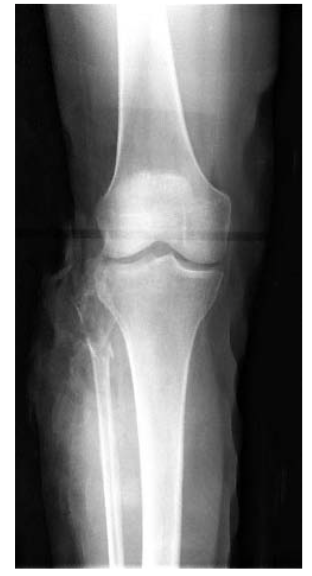

A 38-year-old man comes to the office for follow-up examination two months after undergoing open reduction and internal fixation of a fracture of the right proximal fibula. A preoperative radiograph is shown. On current physical examination, he can evert the right foot, but he is unable to dorsiflex it. This patient has most likely sustained an injury to which of the following nerves?

A ) Common peroneal B ) Deep peroneal C ) Sciatic D ) Superficial peroneal E ) Sural

The correct response is Option B.

The patient described has sustained an injury to his deep peroneal nerve. An electromyelogram should be ordered to confirm the diagnosis. The common peroneal nerve divides into two branches. The deep branch of the peroneal nerve innervates the extensor hallucis longus and the anterior tibial muscles. The superficial branch of the peroneal nerve provides motor innervation to the peroneus longus and brevis muscles. If the common peroneal nerve had been injured, eversion would not have been likely. A sural nerve injury would have a sensory component, not a motor component. The sciatic nerve injury would have more global consequences, though this pattern is theoretically possible in a Sunderland Grade VI injury. Thus, the most likely injured nerve is the deep peroneal nerve.